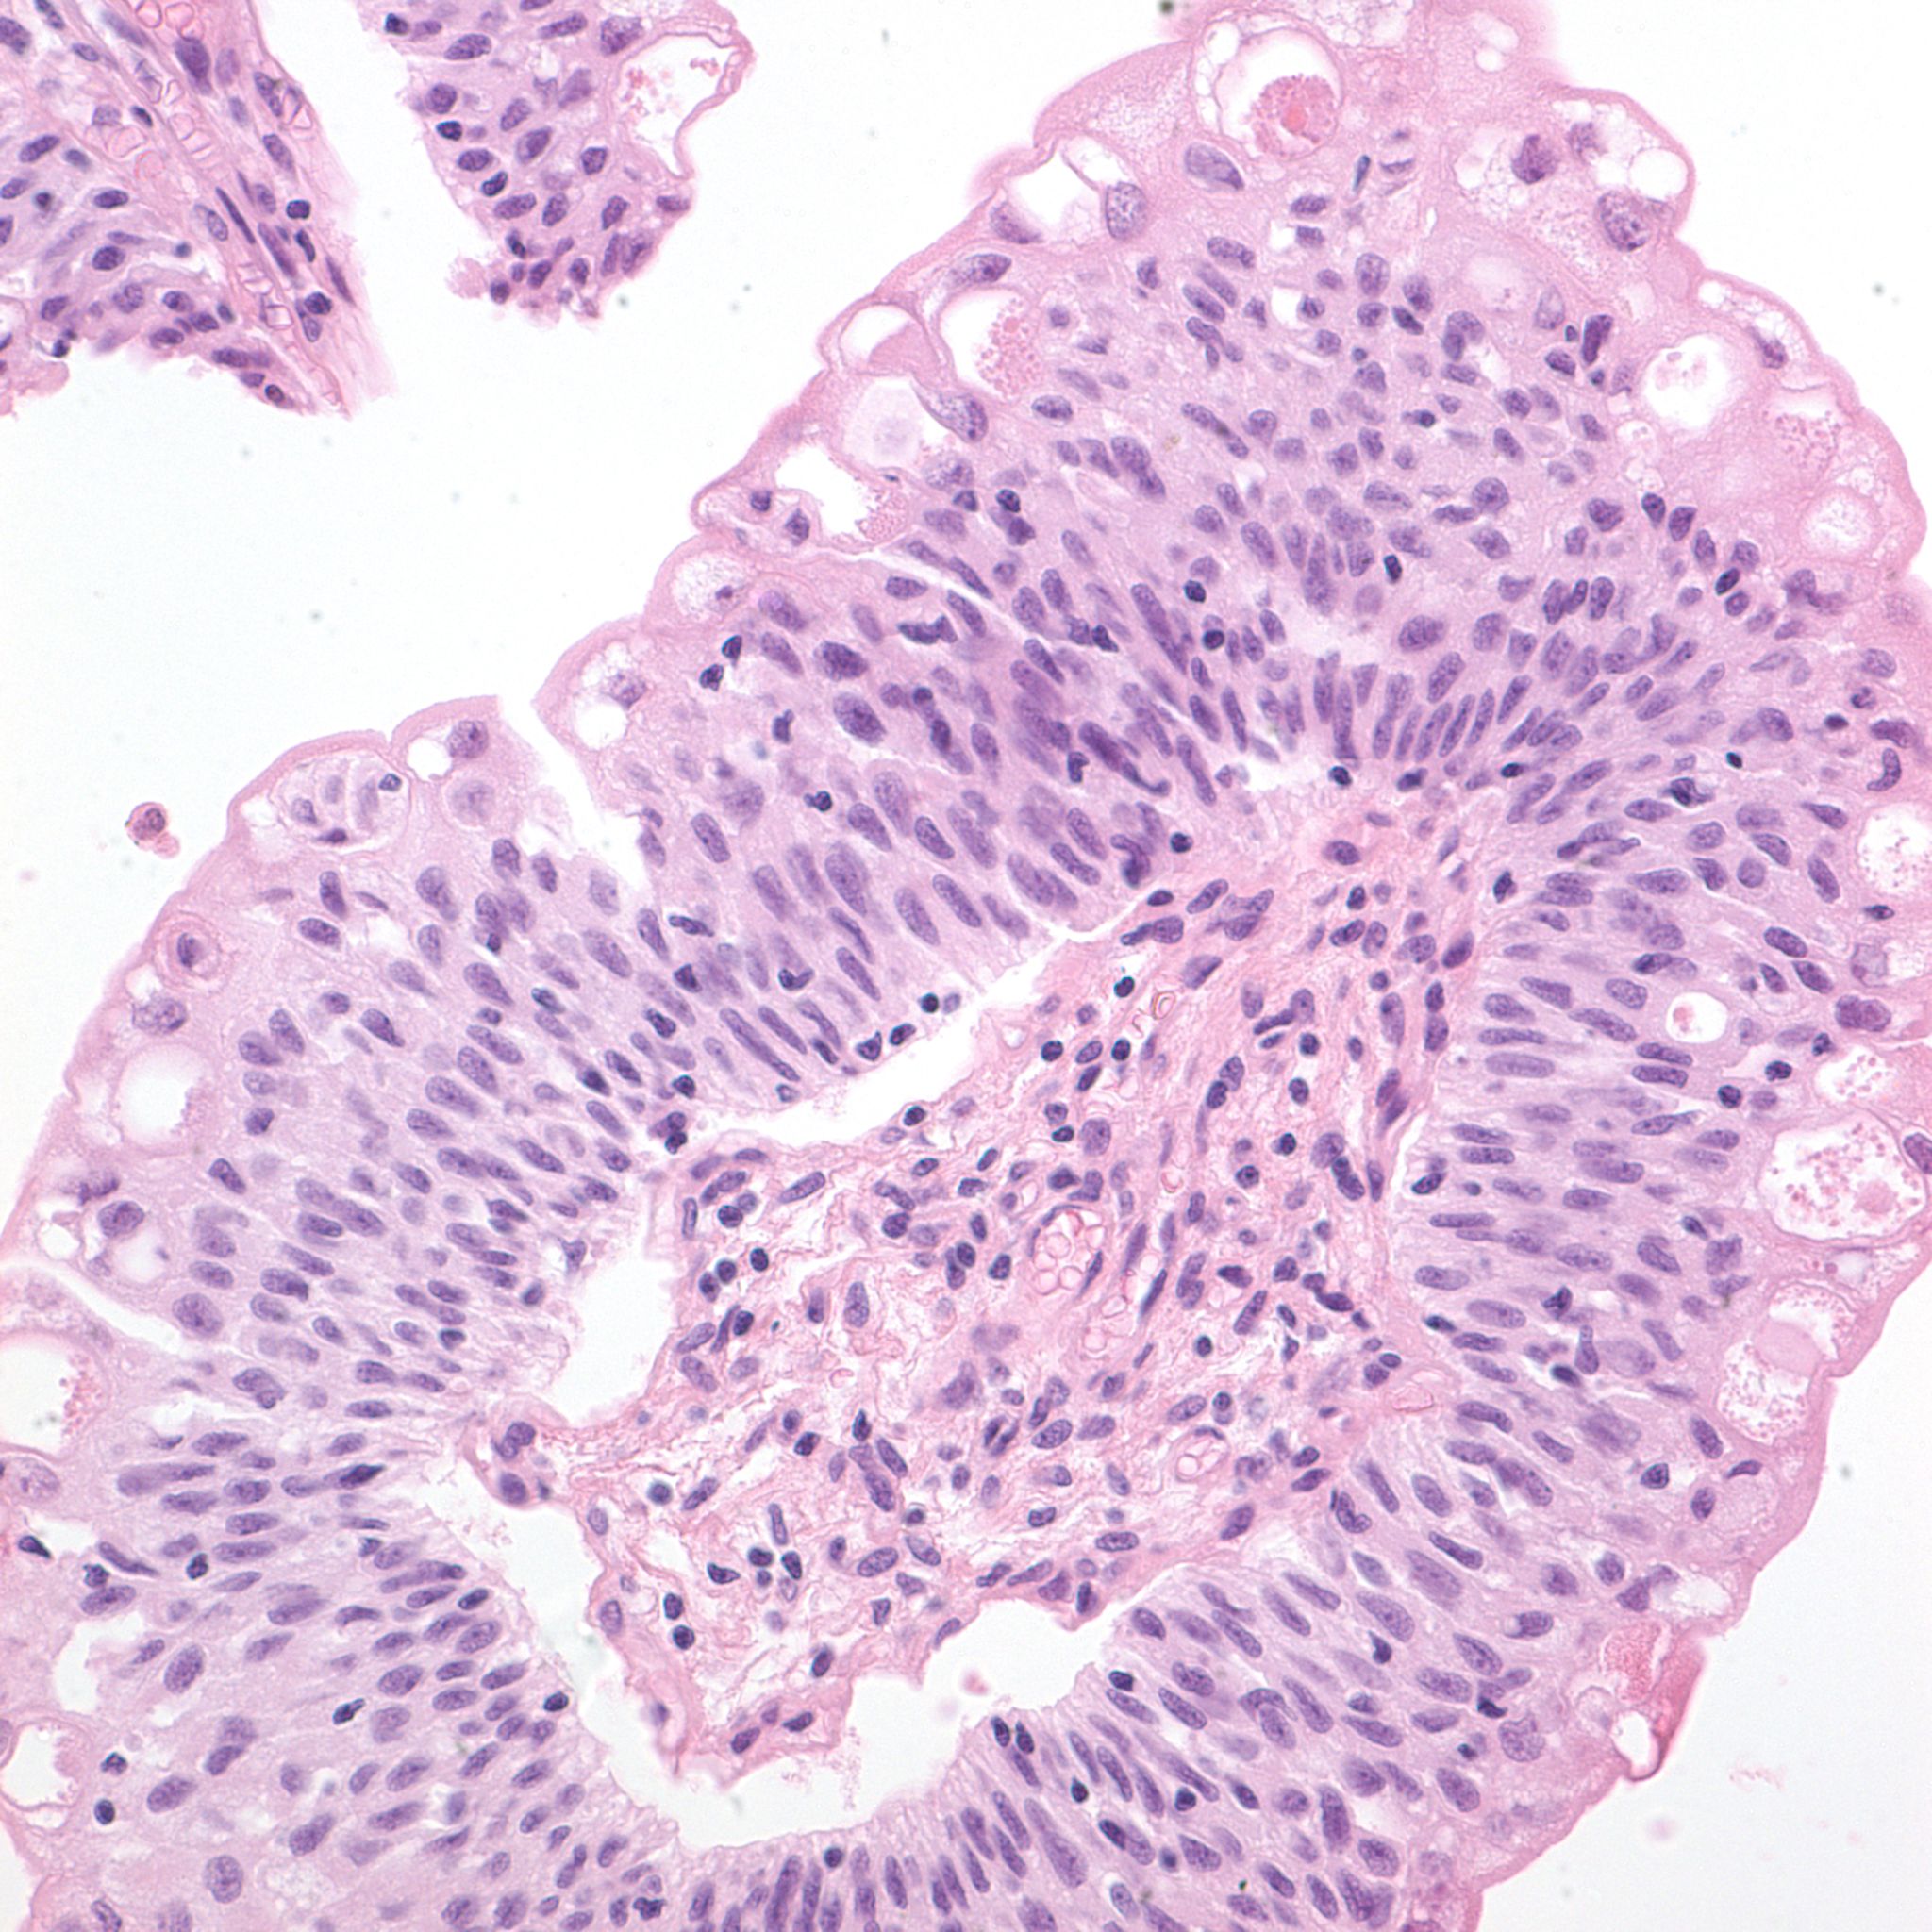

Bladder Papillary Lesions

Case ID: 303